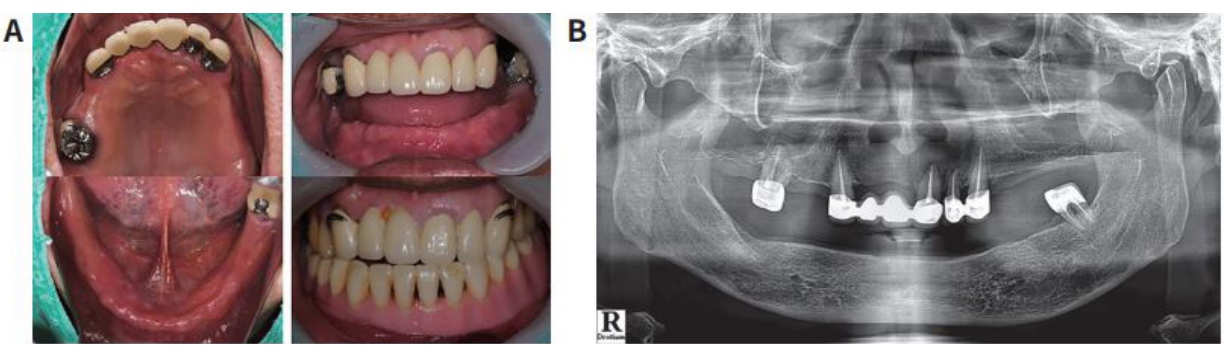

(그림 12) 증례는 60대 환자로 상하악 부분무치악 환자이며,상하악 가철성 국소의치를 사용해 온 상태이나 특히 하악 국소의치가 유지력이 없어 저작시 불편하여 만족을 하지 못하여 내원한 환자이다.

상악: 기존 고정성 보철물(브릿지,크라운)을 그대로 이용한 가철성 국소의치

하악: 임플란트 지지 고정성 보철물 (3개의 Zirconia Bridge)